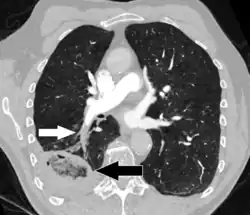

- CT scan of a lung infarction because of chronic pulmonary embolism (white arrow). The infarcted area (black arrow) has a reverse halo sign.